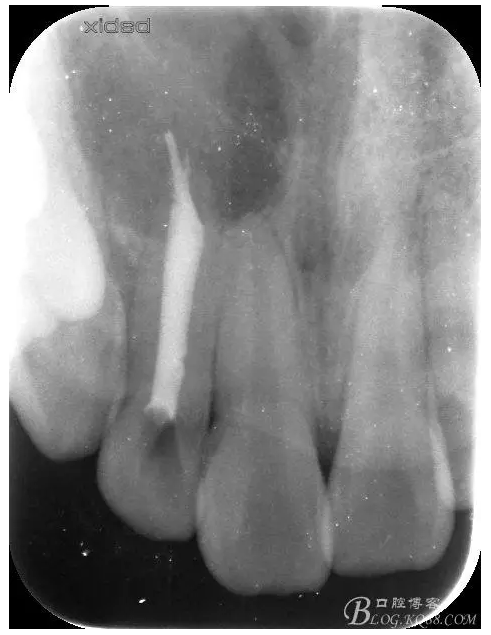

圖4.摘除囊壁后形成的巨大骨腔

圖5.清理骨腔,可以看到12的根尖暴露在骨腔內(nèi)。

圖6.超聲骨刀切除根尖3mm。

圖7.切除根尖3mm的影像